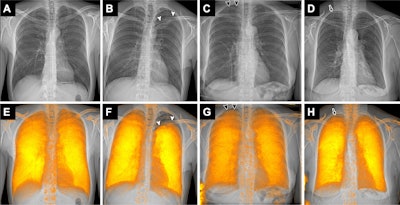

Examples of attenuation-based conventional radiographs (A-D) without and (E-H) with dark-field overlay in a (A, E) 49-year-old male participant without pneumothorax and (B-D, F-G) three participants with pneumothorax. The participants with pneumothorax included (B, F) a 32-year-old male participant with left-sided apical, pronounced pneumothorax (arrowheads), (C, G) a 72-year-old female participant with a small right-sided apical pneumothorax (arrowheads) in whom thoracic drainage has already been inserted on the right side, and (D, H) a 75-year-old female participant with a small right-sided apical pneumothorax (arrow), in whom the pneumothorax is even more obvious on the radiograph with dark-field overlay (arrowheads). (C, G) In the 72-year-old female participant, the pneumothorax line is hard to recognize on the conventional radiograph without overlay (due to overlay of ribs); it appears to be easier to recognize on the image with the dark-field overlay due to the signal loss in that area. (D, H) In the 75-year-old participant, the small pneumothorax is difficult to recognize on both the image without overlay (D) due to ribs in that area, and the image with dark-field overlay (H) due to an ill-defined margin of the dark-field signal combined with residual beam-hardening-induced dark-field signal from the ribs. In G, the dark-field signal in the lower left corner is due to an attached band-aid.RSNA

Dark-field chest radiographs demonstrated clear signal loss in collapsed lung regions of participants with pneumothorax.